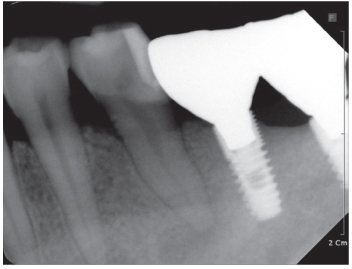

Figure 2

Preoperative panorama view. Periapical radiolucency was observed at the apex of mandibular left second premolar.

Figure 2 Preoperative panorama view. Periapical radiolucency was observed at the apex of mandibular left second premolar.